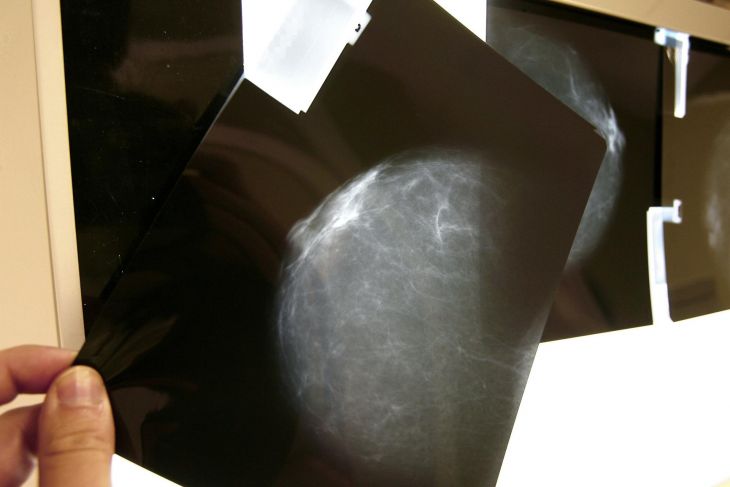

Foto: Efe

“El cáncer de mama ya no es exclusivo para mujeres de 40 años en adelante, la incidencia en jóvenes ha aumentado. Hemos tenido pacientes menores de 30 años”, dijo la doctora Ana Jiménez Coral, jefa del Departamento de Servicios Médicos del Sistema Nacional para el Desarrollo Integral de la Familia (DIF) Yucatán.

De hecho, según el Instituto Nacional de Estadística y Geografía (Inegi), en 2022 la tasa de defunciones de mujeres de 20 a 34 años fue de 1.31 por cáncer de mama, la tasa va en aumento según la edad, hasta llegar a las mujeres de 60 años en adelante con una tasa de mortalidad de 49.33.

La recomendación de prevención es hacer una autoexploración una vez al mes para personas menores de 40 años, y para las mayores de 40 realizarse una mastografía.

Si detectan algún nodo anormal durante la autoexploración, es importante acudir al médico para realizarse un ultrasonido y conocer la composición de la anomalía, pues puede tratarse de un quiste o lipoma, detalló.